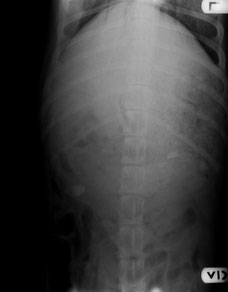

腹背方向の撮影。

胃内容物がいっぱいです。

ウレタン系の接着剤が胃の中でかたまったものの全容です。

幅は20cmくらいあります。